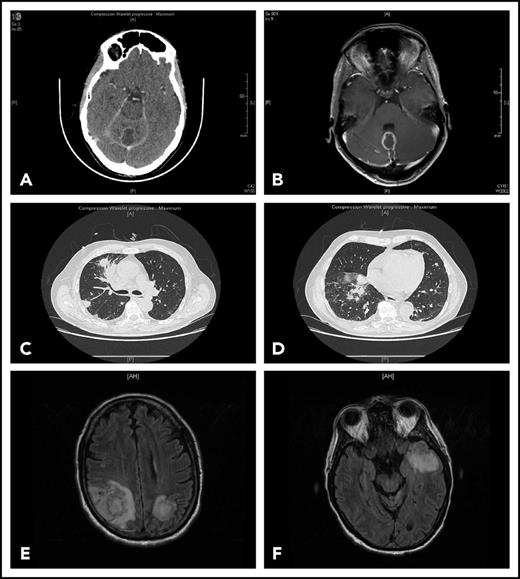

Representative findings in 2 patients with IFI. Patient 1 had been receiving ibrutinib 420 mg/d for 4 months for CLL associated with grade 3 autoimmune neutropenia when she complained of gait disorder. Computed tomography scan (A) and T1-weighted magnetic resonance imaging with gadolinium injection (B) revealed a solitary abscess of the vermis. Neurosurgical drainage disclosed Aspergillus fumigatus. Patient 2 was hospitalized after a third cycle of bendamustine, rituximab, ibrutinib for fever, cough, and confusion. Chest computed tomography scan revealed multiple pulmonary nodules (C-D) and T2-weighted fluid attenuation inversion recovery (FLAIR) magnetic resonance imaging multiple cerebral abscesses (E-F). Aspergillus antigenemia was strongly positive, and Aspergillus fumigatus was isolated in the bronchoalveolar lavage.

Representative findings in 2 patients with IFI. Patient 1 had been receiving ibrutinib 420 mg/d for 4 months for CLL associated with grade 3 autoimmune neutropenia when she complained of gait disorder. Computed tomography scan (A) and T1-weighted magnetic resonance imaging with gadolinium injection (B) revealed a solitary abscess of the vermis. Neurosurgical drainage disclosed Aspergillus fumigatus. Patient 2 was hospitalized after a third cycle of bendamustine, rituximab, ibrutinib for fever, cough, and confusion. Chest computed tomography scan revealed multiple pulmonary nodules (C-D) and T2-weighted fluid attenuation inversion recovery (FLAIR) magnetic resonance imaging multiple cerebral abscesses (E-F). Aspergillus antigenemia was strongly positive, and Aspergillus fumigatus was isolated in the bronchoalveolar lavage.